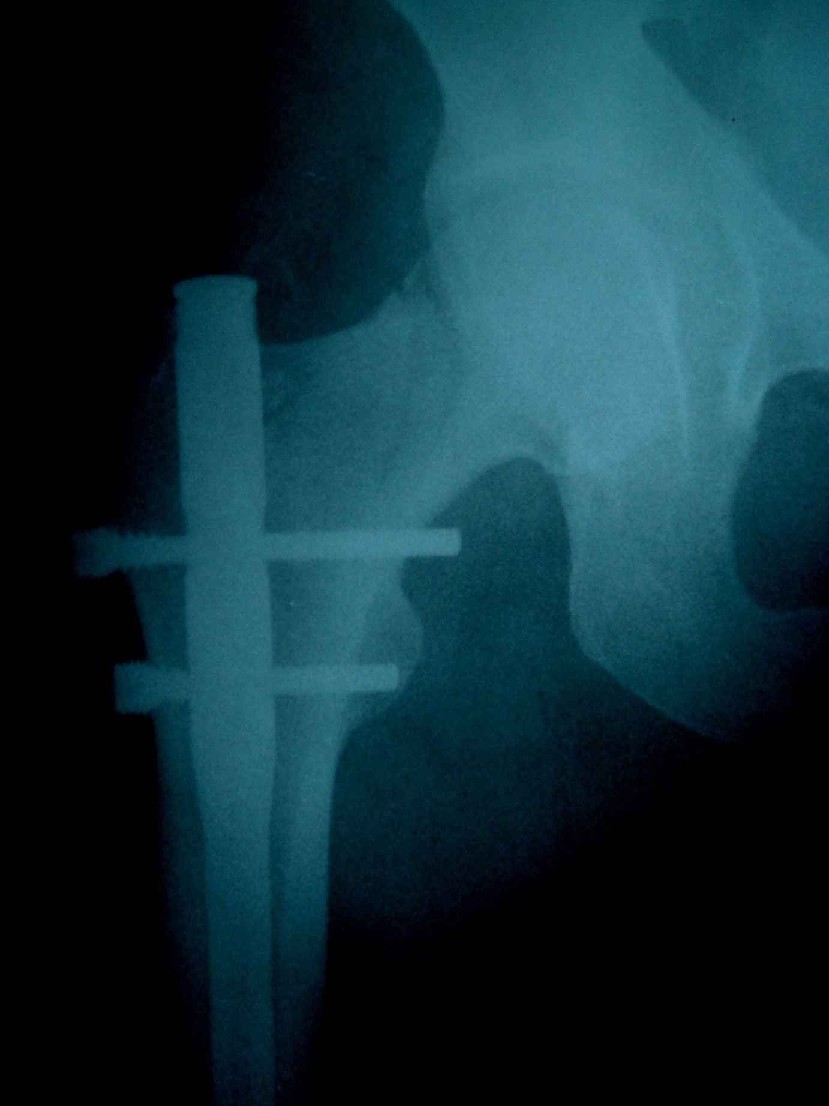

患者,女,因外伤就诊。摄骨盆及右股骨。当时报告骨盆未见明显异常,右股骨中段粉碎性骨折。五天后行股骨中段骨折内固定手术,术中摄床边片示股骨颈骨折。现把术前和术中图像上传。请大家高诊,分析股骨颈骨折是术前漏诊还是其他原因。术前骨盆片右股骨颈显示欠佳是由于股骨中段骨折无法将股骨颈完全显示。

术前片示右股骨颈未见明显骨折征象。如果事先有骨折,由于投照位置原因,骨折线也是完全有可能被挡住重叠而看不见的(并且本例骨折对位良好,更有可能看不到)。所以要凭此判断述前是否有骨折不容易

术前由于位置原因使股骨颈未全部显示,骨折线与股骨头重叠,骨折也可以使股骨颈缩短

回头看术前片,可见一低密透光区.

术前所照的片子体位好象有点不标准,右侧股骨颈显示不是很好,没有完全展开,所以不好说术前就一定没有骨折的情况.

关于楼主说的骨折线的形态,的确和一般外伤的有种不太一样的感觉,上方裂隙较明显,下方骨皮质“连续”,我认为成年人应该是全部断了的,不全骨折的可能性非常非常小,该片恰好无法全部显示骨折线。骨折线的形态不能判定术前还是术后骨折。以上只是个人小小看法,请各位老师指正为谢!